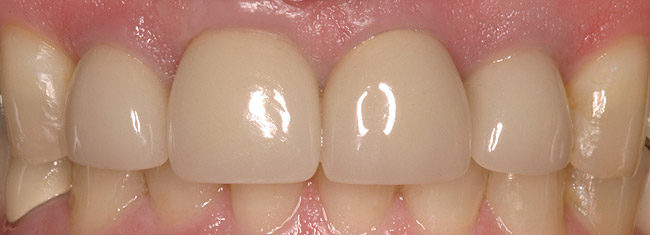

Figure 5a  Congenitally missing lateral incisors. Postorthodontic therapy, prior to implant placement.

Figure 5a

Figure 5b  Congenitally missing lateral incisors. Postorthodontic therapy, prior to implant placement.

Figure 5b

Figure 5d  Completed, porcelain-fused-to-gold implant restorations, custom gold abutments, lingual-set screw-retention, Kerr Extrude¬Æ light-body crown-abutment seal.

Figure 5d

Figure 5e  Completed, porcelain-fused-to-gold implant restorations, custom gold abutments, lingual-set screw-retention, Kerr Extrude¬Æ light-body crown-abutment seal.

Figure 5e

Figure 5f  Completed, porcelain-fused-to-gold implant restorations, custom gold abutments, lingual-set screw-retention, Kerr Extrude¬Æ light-body crown-abutment seal.

Figure 5f

Figure 5g  Completed, porcelain-fused-to-gold implant restorations, custom gold abutments, lingual-set screw-retention, Kerr Extrude¬Æ light-body crown-abutment seal.

Figure 5g

Of all the options presented, when treatment planned and performed to recommended implant surgical and prosthetic guidelines, this option is the most conservative from biological standpoint. The esthetic outcome can be as natural as the tooth it is otherwise replacing (Figure 5).13-15 Patient satisfaction for such successful treatment outcomes is high.16 However, not all patients who are missing a single anterior tooth are ideal candidates for implant therapy. There may be medical contraindications, significant site preparation required, and/or financial constraints. Dental providers may find the resin-bonded or conventional FPD option a more suitable treatment modality with the patient accepting the associated disadvantages and limitations. If this is the case, it is important to have a wider overall treatment outcome picture when comparing the different options.17 From a long-term perspective, few patients perceive real value to either doing nothing or choosing an RPD. Consequently, this leaves the two main contenders: conventional FPD therapy versus single-tooth implant therapy.